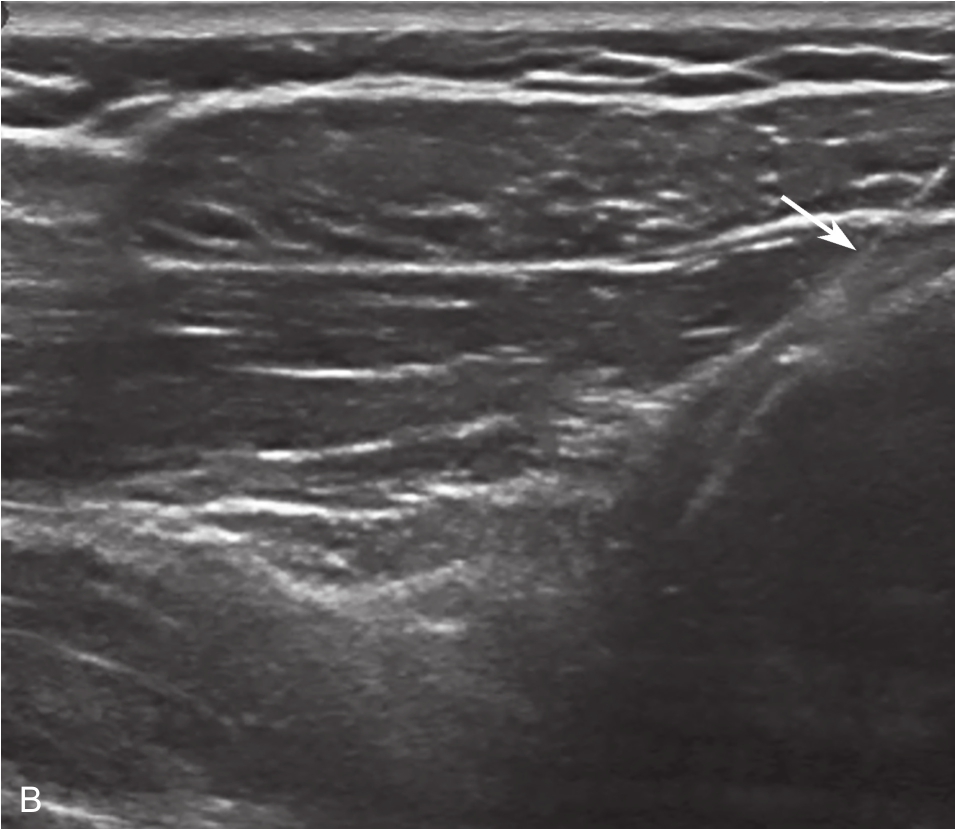

▲ 图2-6-4 超声引导下肩关节腔介入治疗超声图(二)

A.肩关节下关节囊增厚;B.超声引导下穿刺针进入盂肱关节腔

▲ 图 2-6-4(续)

C.超声引导下类固醇及生理盐水注射;D.注射治疗后关节腔扩张;双星号:增厚关节囊;箭头:穿刺针;单星号:关节腔